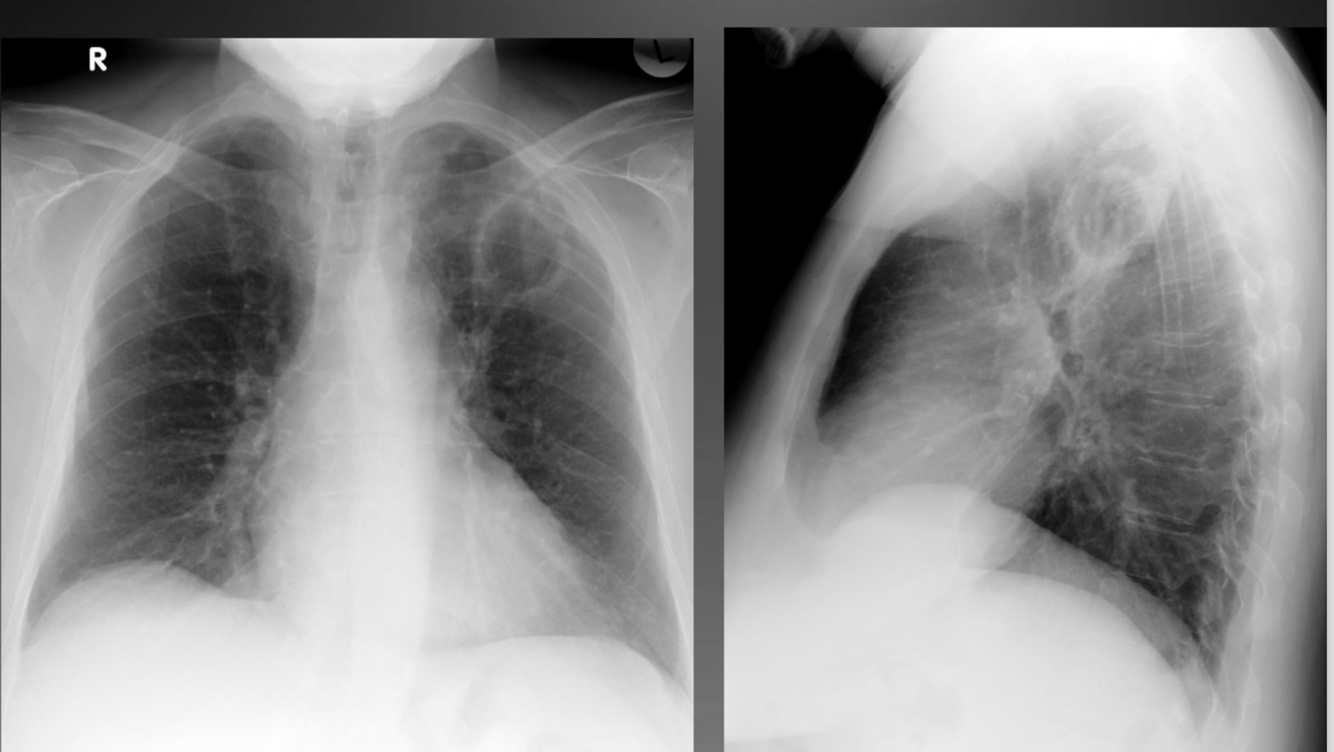

Q

A

Pleural effusion (tb infected)